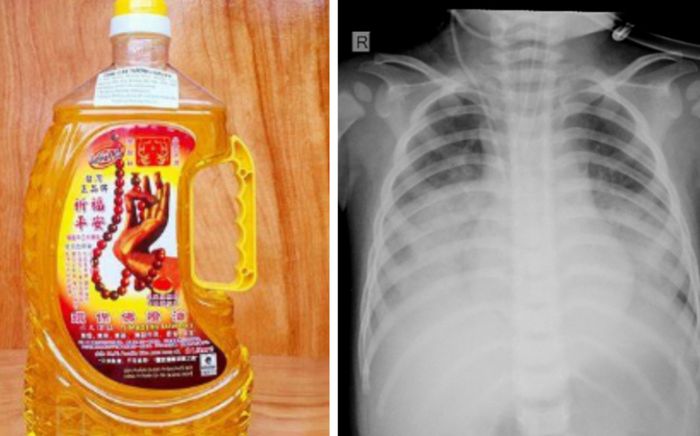

Bé 15 tháng tuổi nguy kịch nhập viện khẩn vì uống nhầm thứ thường thấy ở nhiều gia đình

Sau 4 ngày điều trị, cháu P. (16 tháng tuổi) đã qua cơn nguy kịch và ổn định sức khỏe trở lại.